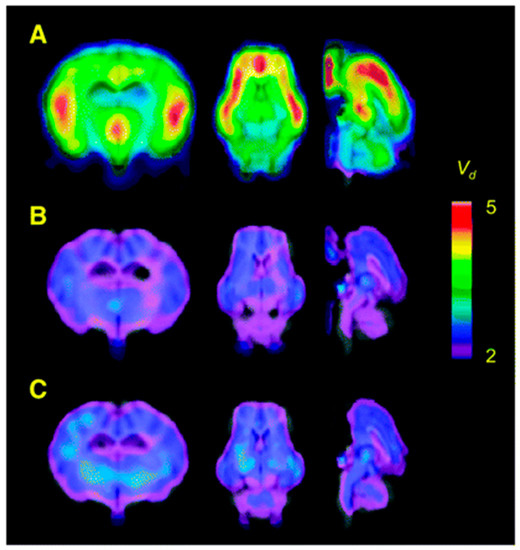

- Arponen, E.; Helin, S.; Marjamäki, P.; Grönroos, T.; Holm, P.; Löyttyniemi, E.; Någren, K.; Scheinin, M.; Haaparanta-Solin, M.; Sallinen, J.; et al. A PET tracer for brain α2C adrenoceptors, 11C-ORM-13070: Radiosynthesis and preclinical evaluation in rats and knockout mice. J. Nucl. Med. 2014, 55, 1171–1177. [Google Scholar] [CrossRef]

- Finnema, S.J.; Hughes, Z.A.; Haaparanta-Solin, M.; Stepanov, V.; Nakao, R.; Varnäs, K.; Varrone, A.; Arponen, E.; Marjamäki, P.; Pohjanoksa, K.; et al. Amphetamine decreases α2C-adrenoceptor binding of [11C]ORM-13070: A PET study in the primate brain. Int. J. Neuropsychopharmacol. 2015, 18, 1–10. [Google Scholar] [CrossRef] [PubMed]